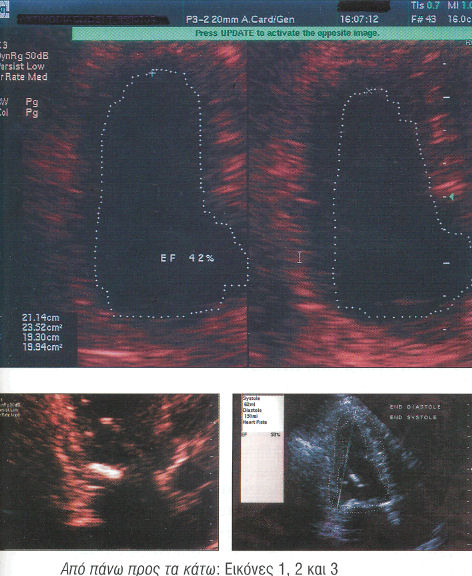

Στο triplex καρδιάς παρουσίασε κλάσμα εξώθησης 42% (εικόνα 1) και σοβαρού βαθμού ανεπάρκεια μιτροειδούς βαλβίδας (εικόνα 2). Θεραπευτικά αυξήθηκαν οι δόσεις των χρησιμοποιημένων φαρμάκων ενώ παράλληλα δόθηκε και ομοιοπαθητική αγωγή.

Σε χρονικό διάστημα 12 ημερών από την έναρξη των ομοιοπαθητικών το triplex καρδιάς έδειξε θεαματική βελτίωση του κλάσματος εξώθησης 59% (εικόνα 3) και της ανεπάρκειας της μιτροειδούς. Η βελτίωση αυτή παραξένεψε πολύ τον καρδιολόγο του σε τόσο σύντομο χρονικό διάστημα γιατί με μόνο τα χημικά καρδιολογικά φάρμακα θα την περίμενε σε διάστημα 20-30 ημερών.